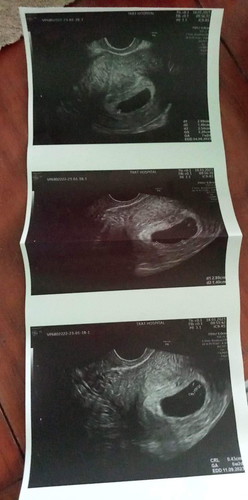

ตอนไปซาวด์ครั้งล่าสุดคุณหมอบอกว่ายังไม่เจอหัวใจน้องนะคะ แต่เจอตัวน้องน้องตัวโตกว่ารอบที่แล้วอยู่นะคะ คุณแม่ น้องอาจจะตัวเล็ก ต้องซาวด์ดูอีกรอบค่ะ หากน้องไม่โตขึ้นกว่านี้ก็อาจจะเกิดความผิดปรกติค่ะต้องยุติ แต่ประจำเดือนของเรามาไม่ปรกติแบบนี้เกี่ยวกับอายุครรภ์ไหมค่ะแบบไข่ตกช้าแบบนี้ค่ะ ขอความคิดเห็นแม่ๆๆหน่อยค่ะ